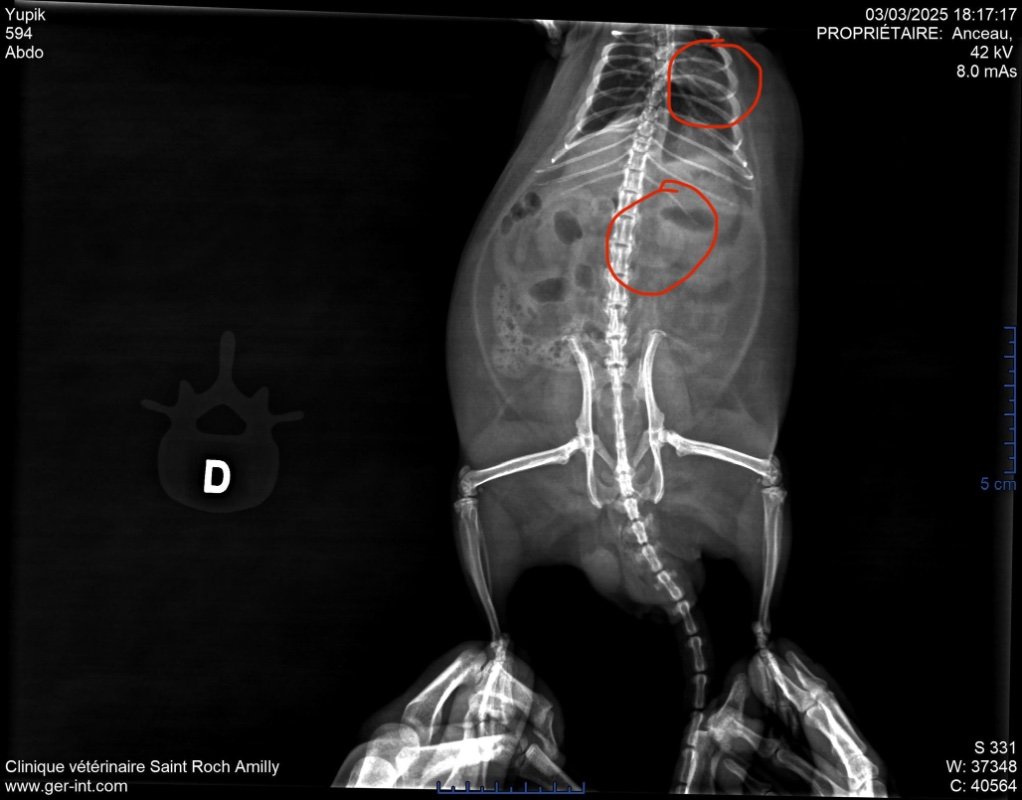

Résultats de la radio :

Présence d’une masse au niveau de l’estomac, vers la sortie de l’estomac. C’est en appuyant à cet endroit qu’il ronfle et fait des pouics, parfois même un éternuement.

Une autre masse a été détectée près du cœur, au-dessus des poumons.

On ne sait pas si ces masses sont cancéreuses, mais il n’est pas prévu de faire un scanner.